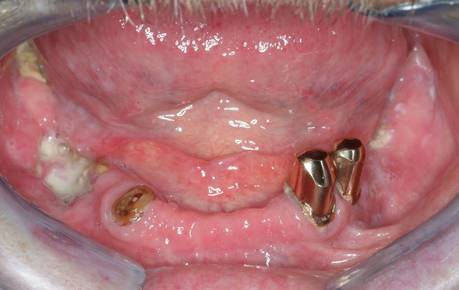

Unter Knochennekrose (Osteonekrose) versteht man eine Erkrankung, bei der Teile eines Knochens oder der gesamte Knochen absterben. Im Kopf- und Halsbereich sind Ober- und Unterkiefer hiervon am häufigsten betroffen. Bis vor wenigen Jahren war die häufigste Ursache für das Absterben von Kieferknochen eine vorausgegangene Bestrahlung im Kieferbereich. Die abgestorbenen Knochenareale wurden als Osteoradionekrose bezeichnet. Durch die in den letzten Jahren zunehmend breite Anwendung von Bisphosphonaten bei der Therapie von Knochenmetastasen (z.B. als Folge von Brust- oder Prostatakarzinomen) und bei der Osteoporosetherapie haben diese Medikamente heute die größte Bedeutung für die Entstehung von Kiefernekrosen. Dieses Krankheitsbild, welches der Osteoradionekrose stark ähnelt, wird Bisphosphonat-assoziierte Osteonekrose oder BONJ (bisphosphonate-associated osteonecrosis of the jaw) genannt. Auch die kürzlich für die Krebstherapie zugelassenen Antikörper Denosumab und Bevacizumab können zur Osteonekrose von Kieferanteilen führen. Eine Kiefernekrose zeichnet sich unter anderem aus durch freiliegenden, nicht von Schleimhaut bedeckten Kieferknochen, zunehmende, scheinbar grundlose Zahnlockerungen, Eiteraustritt aus dem Kiefer oder auch durch Kieferbrüche ohne erkennbare äußere Einwirkung oder Ursache.

Knochennekrosen des Ober- und Unterkiefers treten gerne als Nebenwirkung bei der Einnahme von Medikamenten gegen Knochenstoffwechselstörungen (Osteoporose) und Tumoren (z.B. bösartige Tumoren der Brustdrüse und der Prostata) auf. Während diese Nebenwirkung früher nur den Bisphosphonaten (Diphos®, Didronel®, Etidronat 200®, Bonefos®, Ostac®, Skelid®, Aredia®, Fosamax®, Bondranat®, Actonel®) zugerechnet wurde, zeigen sich inzwischen ähnliche Kiefernekrosen auch unter oder nach Therapie mit Prolia® und XGEVA® (Denosumab, RANKL-Antikörper) sowie Avastin® (Bevacizumab, VEGF-Antikörper). Im Englischen  wird daher auch von MRONJ (medication-related osteonecrosis of the jaw) gesprochen. Gelangen zusätzlich zur Einnahme dieser Medikamente Bakterien ins Knochengewebe (z.B. durch von den Zähnen ausgehende Infektionen, Prothesendruckstellen oder zahnärztliche Eingriffe), können sich diese im geschädigten Knochen schnell ausbreiten und ausgedehnte Entzündungen verursachen. Begünstigend wirken eine dünne Schleimhautbedeckung und eine geringe Durchblutung. So ist der Unterkiefer doppelt so häufig wie der gefäßreichere Oberkiefer betroffen. Die Wahrscheinlichkeit dieser Medikamentennebenwirkung steigt mit zunehmender Behandlungsdauer, steigender Medikamentendosis und ist zusätzlich vom Medikament selbst abhängig. Hochwirksame, moderne Bisphosphonate (sog. Amino-Bisphosphonate) oder die i.v.-Medikamentengabe (im Gegensatz zur Tabletten-Einnahme) haben ein höheres Risikoprofil. Weitere Risikofaktoren sind hohes Alter, Nikotinkonsum und eine schlechte Mundhygiene. Da die Medikamentengabe aufgrund der ursächlichen Grunderkrankung häufig nicht pausiert werden kann und die Wirkung der Medikamente sehr lange anhält (oft viele Monate bis Jahre), sollten  unter laufender Therapie mit diesen Substanzen zahnärztliche und insbesondere zahnärztlich-chirurgische Eingriffe nur unter antibiotischem Schutz erfolgen und eine plastische Deckung des Kieferknochens mit Schleimhaut zwingend beinhalten. Um eine spätere Verschleppung von Bakterien in den geschwächten Knochen zu verhindern, sollten prophylaktisch vor der Einleitung einer Therapie mit Bishosphonaten oder den o.g. Antikörpern alle potentiellen Infektionsherde im Kiefer fachmännisch beseitigt werden.

Ist es, egal durch welche der o.g. Ursachen, zu einer sichtbaren Kiefernekrose gekommen, so sind, je nach Schweregrad bzw. Ausprägung verschiedene therapeutische Schritte notwendig, um eine weitere Ausbreitung der Nekrose und zunehmende Schmerzen, aber auch eine drohende Kauunfähigkeit zu verhindern. In den meisten Fällen ist eine alleinige antibiotische Therapie und lokale Wundpflege mit antibakteriellen Mundspüllösungen nicht ausreichend, da der betroffene Kieferabschnitt nicht mehr zur Regeneration fähig ist. Der abgestorbene Knochenanteil muss vielmehr chirurgisch abgetragen und der darunter liegende, noch gesunde, blutende Kieferabschnitt sicher mit Schleimhaut bedeckt werden. Zudem erhalten Patienten symptomorientiert eine Schmerztherapie. Zusätzlich kann eine hyperbare Sauerstofftherapie, wie sie zur Steigerung des Sauerstoffangebots im Gewebe angewendet wird, ergänzend angewendet werden. Trotzdem bleibt der weitere Krankheitsverlauf nicht selten ungewiss. Bei schwereren Verläufen oder bei nicht seltenem, nach wenigen Wochen oder Monaten Wiederaufflammen der Nekrose muss weiter chirurgisch interveniert werden. Abgekapselte nekrotische Areale (sog. Sequester) müssen entfernt werden. Umfasst die Nekrose die gesamte vertikale Ausdehnung des Unterkiefers, muss gegebenenfalls ein kompletter Kieferabschnitt entfernt werden (sog. Kontinuitätsresektion). Die Kontinuität des Kiefers wird in solchen Fällen zunächst durch Platten und Schrauben vorübergehend wieder hergestellt. Kommt es nach dieser chirurgischen Maßnahme zu keinem Wiederaufflammen der Nekrose im Randbereich der Kieferstümpfe, kann nach wenigen Wochen eine knöcherne Rekonstruktion erwogen werden (z.B. durch Verpflanzung von körpereigenem Knochen aus dem Becken, dem Wadenbein oder dem Schulterblatt).